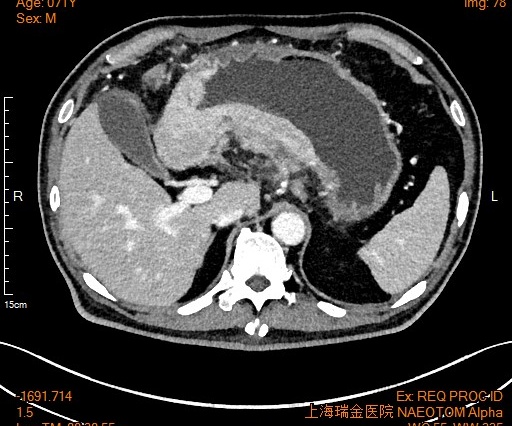

经过3个周期化疗,影像报告显示,老沈肿瘤体积明显缩小,原本存在的转移灶全都消失。营养状况也明显好转,血红蛋白恢复了正常。刘文韬医生团队为老沈做了根治性胃癌切除手术,他很快可以正常饮食,出院回家了。更令人欣喜的是,病理报告提示,癌细胞消失了!显微镜下找不到一点癌细胞的残留。

前后对比肿瘤变化